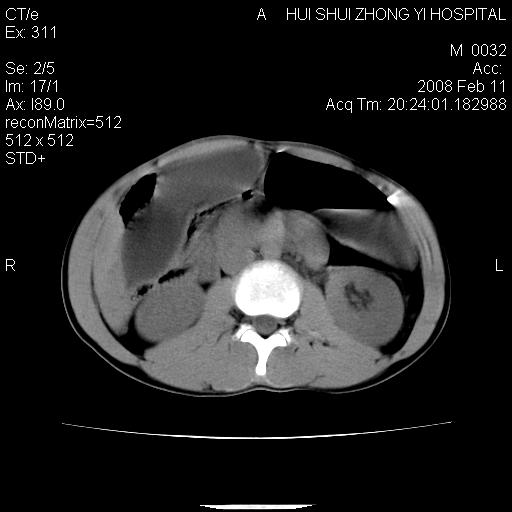

标题: CT11660:男,16岁,现腹痛剧烈,现发烧、头痛、恶心呕吐 [打印本页]

标题: CT11660:男,16岁,现腹痛剧烈,现发烧、头痛、恶心呕吐

8年前曾在贵洲省人民医院b超诊断为肝内胆管结石。现腹痛剧烈,现发烧、头痛、恶心呕吐县医院b超示胆囊肿大大小159*46mm,囊内见6*5mm强回声光团,胆各总管内径56mm。提示:胆囊结石、急性胆囊炎、胆总管重度扩张。

胆囊结石.急性胆囊炎.重度胆管扩张.右侧胸腔少量积液,建议ct增强

考虑先天性胆管囊肿;胆囊增大并结石。右侧胸腔少量积液,建议ct增强。

caroli囊肿并囊内结石。胆囊增大并胆结石。典型!

先天性胆管囊肿,胆囊结石、胆囊增大,右侧少量胸腔积液。